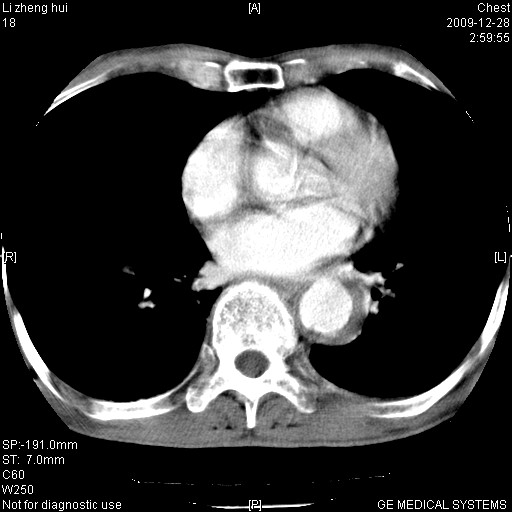

标题: CT23859:胸主动脉瘤

男  79岁 胸部痛急诊入院,晚上做的增强

考虑主动脉瘤?(增粗、钙化、壁血栓?)

动脉瘤伴附壁血栓

1)考虑胸主动脉壁间血肿或夹层动脉瘤。2)多发性肝囊肿。

1)考虑胸主动脉附壁血栓或夹层动脉瘤。2)多发性肝囊肿。